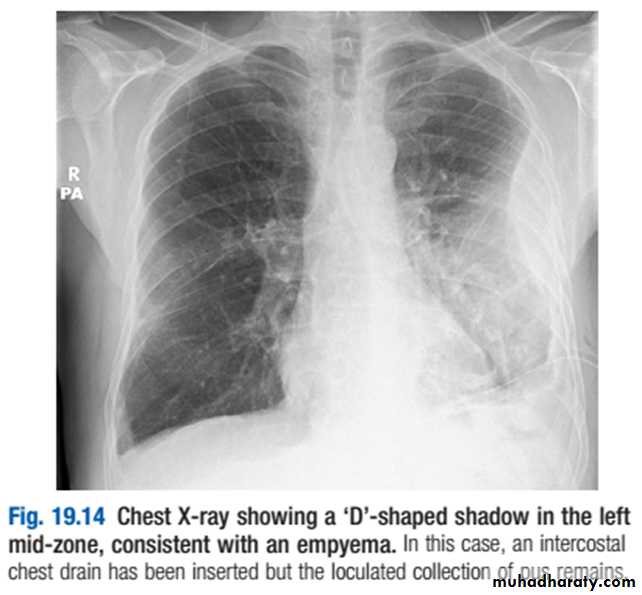

Chest X-ray appearances may be indistinguishable from those of pleural effusion, although pleural adhesions may confine the empyema to form a ‘D’-shaped shadow against the inside of the chest wall .When air is present as well as pus (pyopneumothorax), a horizontal ‘fluid level’ marks the air/liquid interface.Ultrasound shows the position of the fluid, the extent of pleural thickening and whether fluid is in a single collection or multiloculated, containing fibrin and debris .